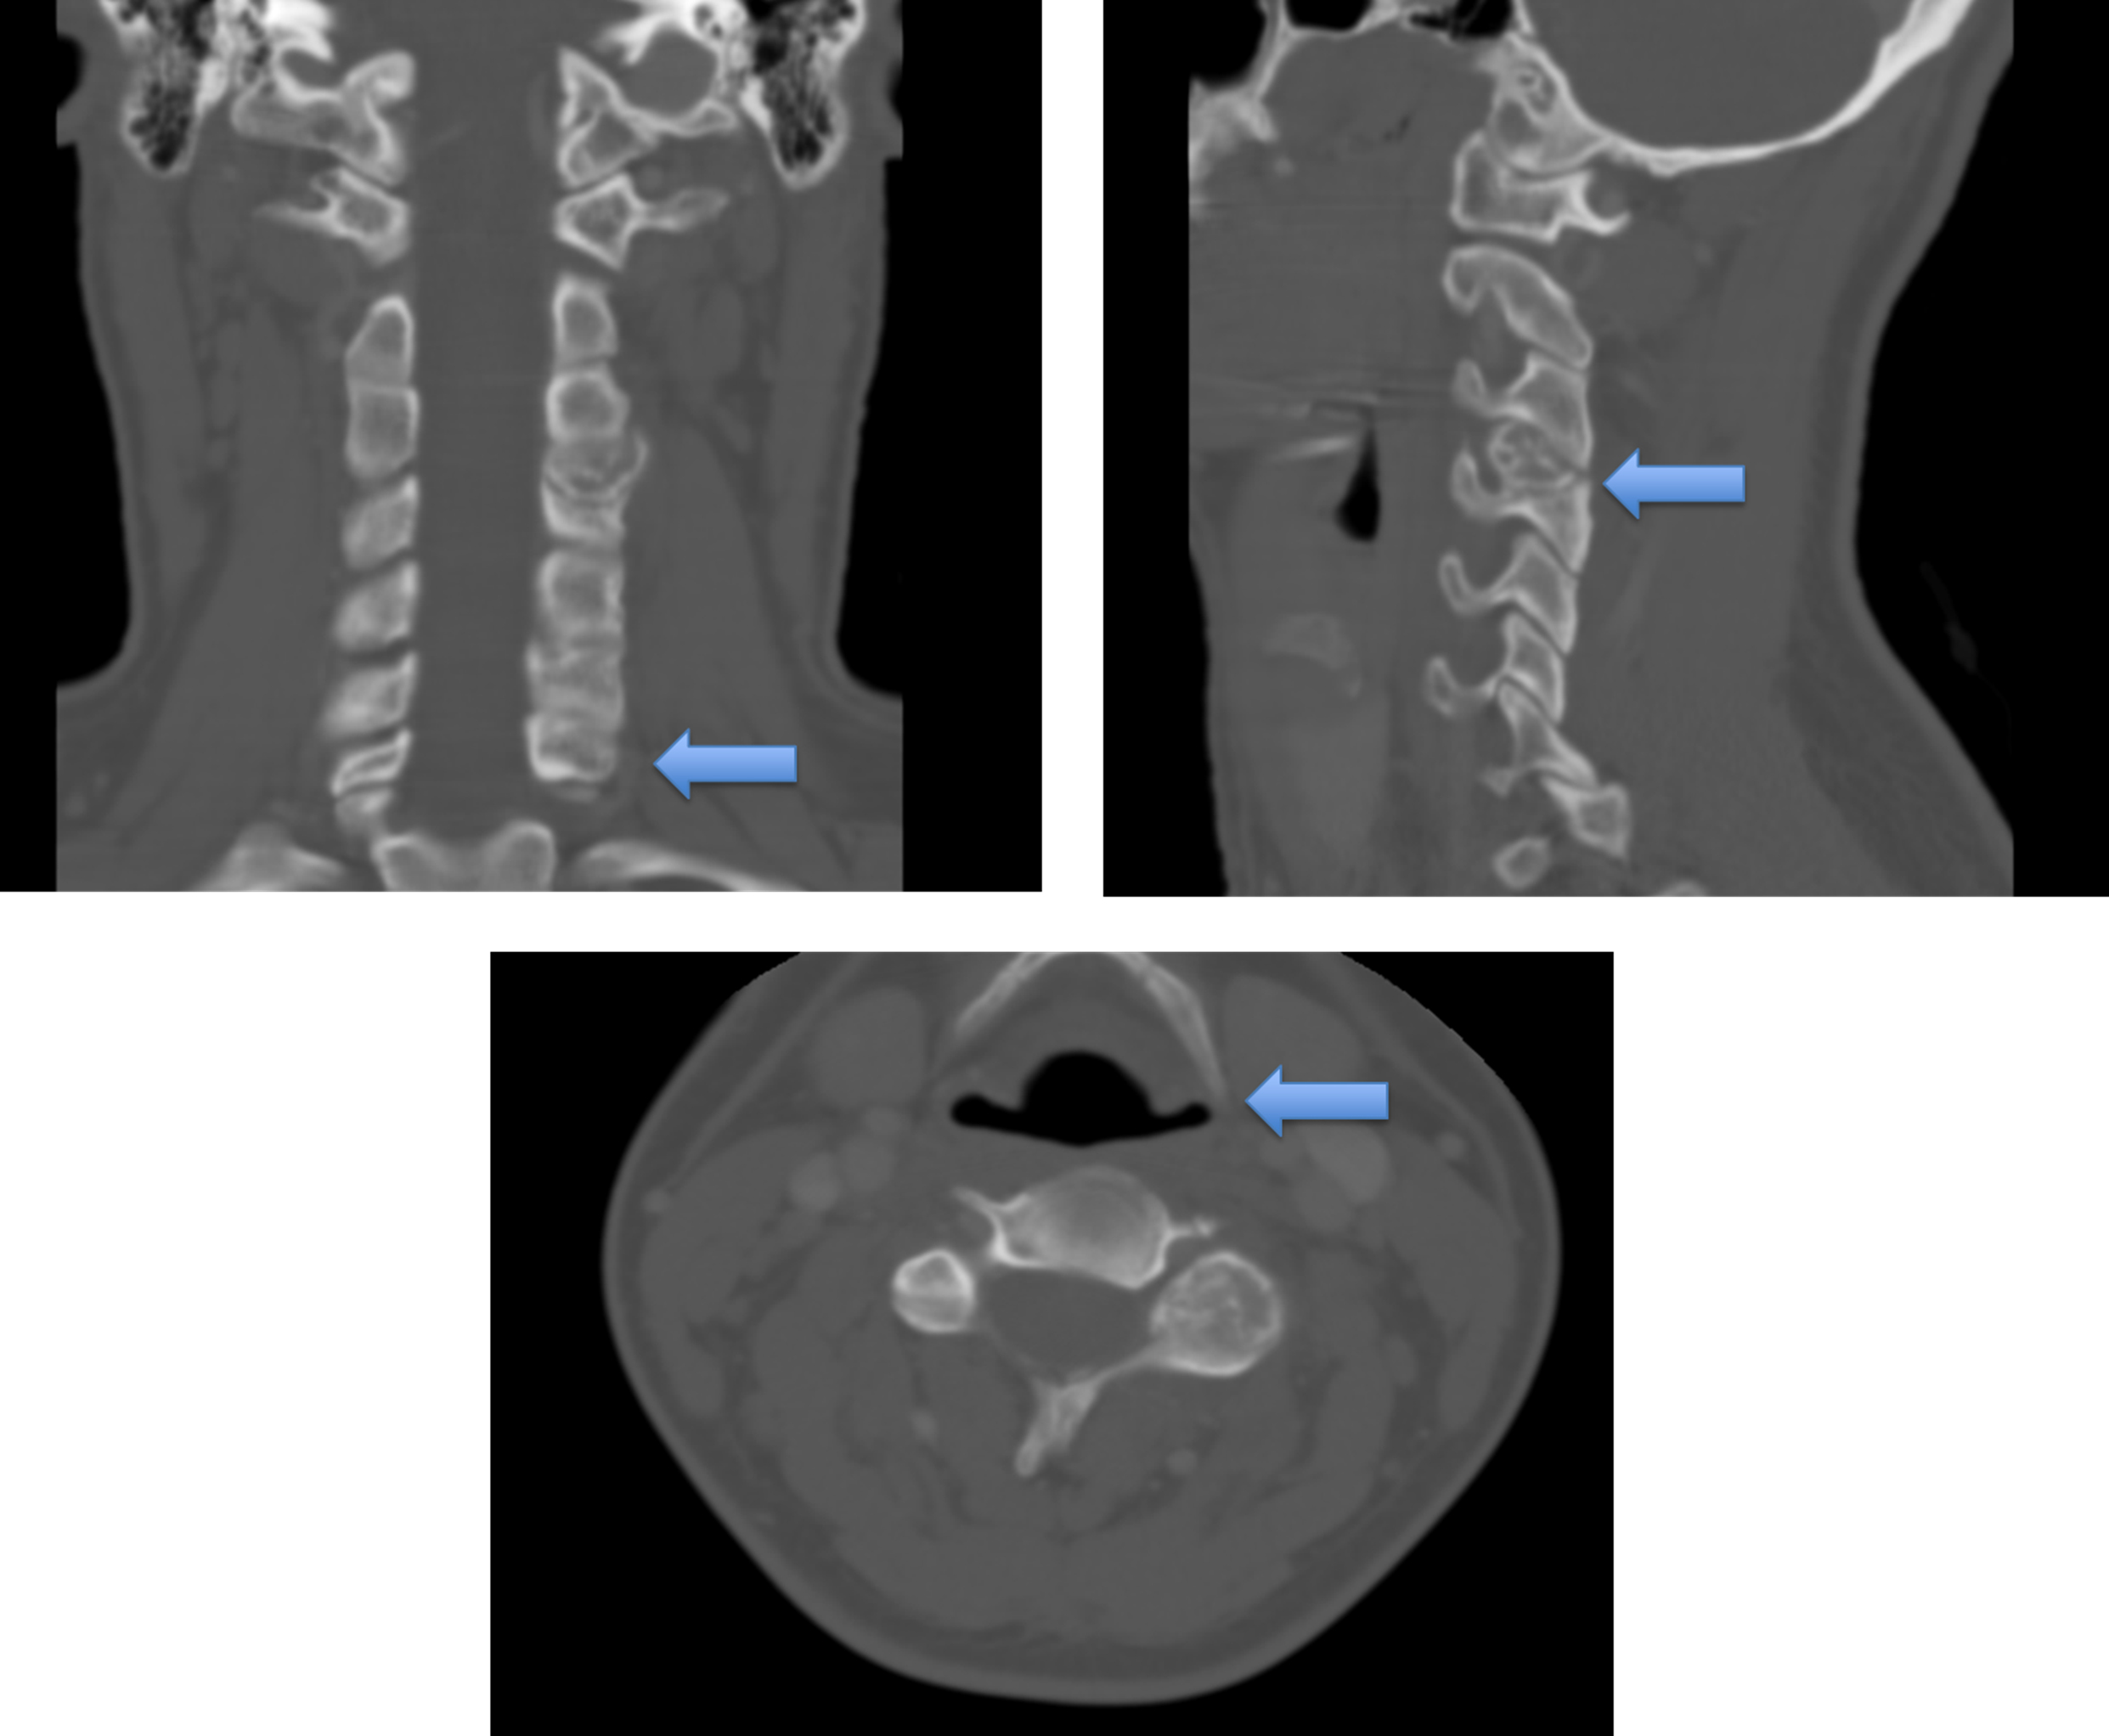

Estudios imagenológicos

Imágenes prequirúrgicas

Radiológicamente, los cordomas se observan como lesiones solitarias de la línea media, destructoras de hueso. La resonancia magnética es ideal para su diagnóstico, con hallazgos que en T1 suelen verse como lesiones isohipointensas; mientras que en T2 se ven hiperintensas y con realce con gadolinio [11]. La resonancia magnética permite valorar la extensión a tejidos blandos o estructuras vecinas, y su relación con estructuras anatómicas. La tomografía axial computarizada muestra afectación ósea con imágenes de una lesión ósea lítica que puede tener un componente mixto sólido-líquido con calcificaciones en un 30-70 % de los casos, por secuestro del hueso [12,13].